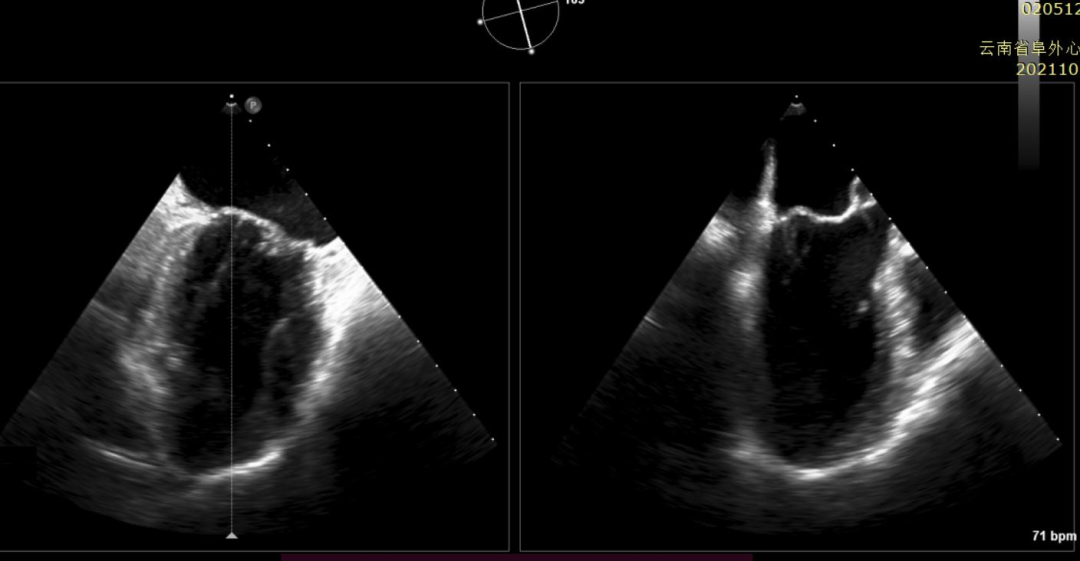

患者为年愈6旬老年男性,因反复心累气紧入院,伴双下肢进行性水肿,入院诊断:二尖瓣重度关闭不全,心功能III级,合并心房颤动,甲状腺功能减退,严重的慢性阻塞性肺部疾病等并发症。心超提示:左心房增大,左心室增大,心功能降低,肺动脉高压,瓣环扩张,前后瓣叶脱垂,二尖瓣复合病变(FMR合并DMR)。

经过云南阜外医院结构性心脏病MDT团队综合讨论评估该患者病情后,患者为传统手术高危患者,瓣膜病变解剖无法行介入修复,决定进行MitraFix™经心尖二尖瓣植入。术前心脏CTA二尖瓣D形瓣环面积折算直径34mm, 模拟植入34号介入二尖瓣膜(外经约40mm)后左心室NeoLOVT面积可(>150mm2)。手术在单纯超声引导下完成,采用左侧肋间4cm微创切口心尖入路,在超声引导下,输送系统准确跨瓣,并将瓣膜准确释放于二尖瓣瓣瓣环,瓣膜释放后支架贴合牢固,无瓣周漏及瓣内反流,二尖瓣前向血流通畅,平均压力阶差2mmHg,左心室流出道通畅,流出到血流速度为2.3m/s,平均压力阶差8mmHg(图2-3,视频1)。顺利撤出输送系统,关闭心尖切口,手术顺利结束。

图2:术中TEE见左心增大,收缩期瓣叶广泛脱垂,心功能降低